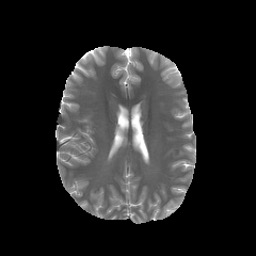

Denoising diffusion probabilistic models (DDPMs) have achieved unprecedented success in computer vision. However, they remain underutilized in medical imaging, a field crucial for disease diagnosis and treatment planning. This is primarily due to the high computational cost associated with (1) the use of large number of time steps (e.g., 1,000) in diffusion processes and (2) the increased dimensionality of medical images, which are often 3D or 4D. Training a diffusion model on medical images typically takes days to weeks, while sampling each image volume takes minutes to hours. To address this challenge, we introduce Fast-DDPM, a simple yet effective approach capable of improving training speed, sampling speed, and generation quality simultaneously. Unlike DDPM, which trains the image denoiser across 1,000 time steps, Fast-DDPM trains and samples using only 10 time steps. The key to our method lies in aligning the training and sampling procedures. We introduced two efficient noise schedulers with 10 time steps: one with uniform time step sampling and another with non-uniform sampling. We evaluated Fast-DDPM across three medical image-to-image generation tasks: multi-image super-resolution, image denoising, and image-to-image translation. Fast-DDPM outperformed DDPM and current state-of-the-art methods based on convolutional networks and generative adversarial networks in all tasks. Additionally, Fast-DDPM reduced training time by a factor of 5 and sampling time by a factor of 100 compared to DDPM. Our code is publicly available at: https://github.com/mirthAI/Fast-DDPM.